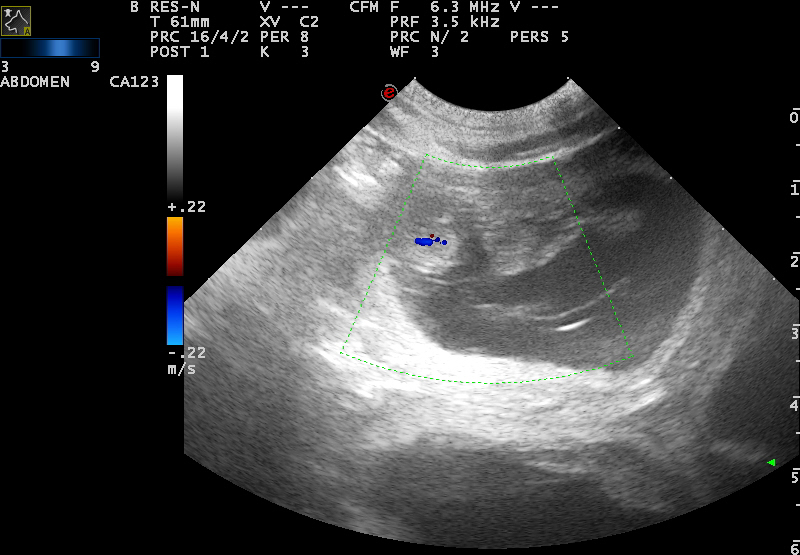

10. Februar 2025 – Der Ultraschall hat es bestätigt 🙂

Wir haben es schon lange vermutet. Scully hat alle Anzeichen gezeigt, die eine tragende Hündin haben kann. Unsere kleine «Rakete» wurde wortwörtlich zur «Schlaftablette». Ständig wurden Kuscheleinheiten eingefordert. Sie wurde mäkelig beim Fressen…

Heute war der Ultraschalltermin, und ja, sie ist tragend. Die Ärztin prophezeit einen größeren Wurf. Wir sind sehr gespannt, ob die Welpenanzahl «zweistellig» sein wird. Jetzt hoffen wir erst einmal weiterhin auf eine unbeschwerte Trächtigkeit.

Hier ein paar Impressionen: